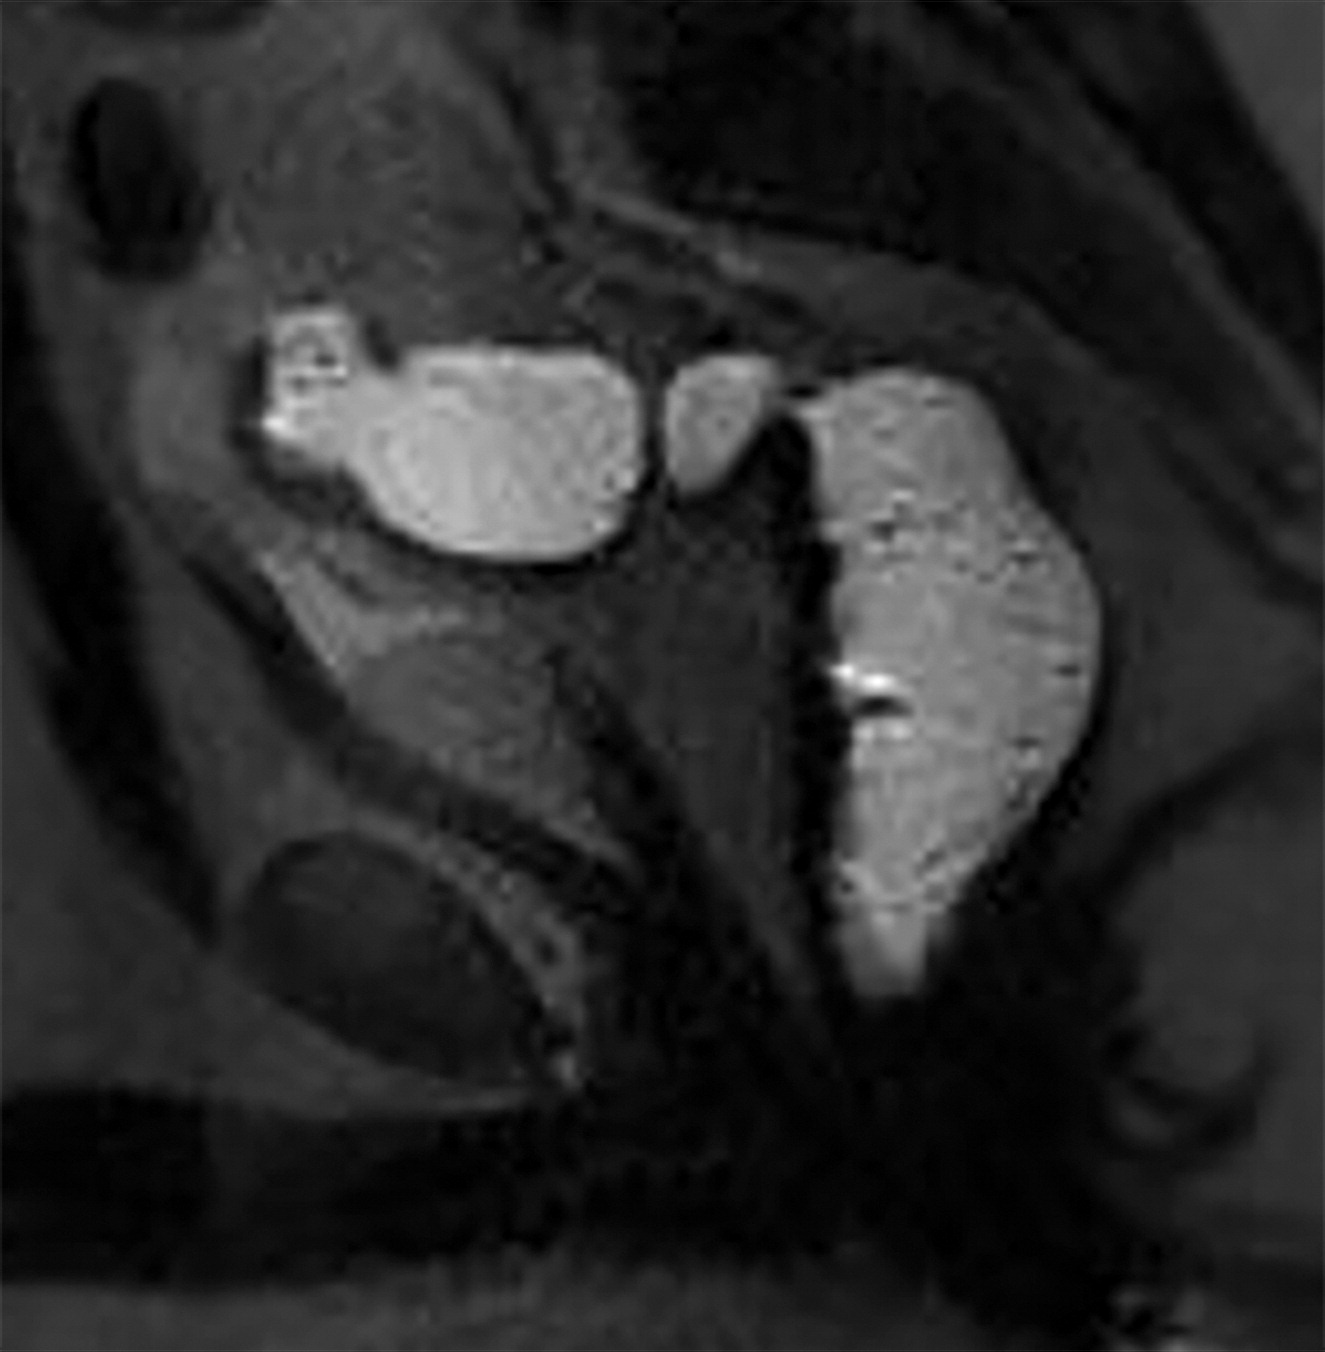

45d202b8c9b68c9a5a2f56b9e29f9039.jpeg709dc23c4aabdb61c1873e30f3ca4c92.jpeg

尿道吊带。

白色长箭头示尿道吊带的正常位置,正常的尿道吊带是薄的T2WI低信号影,向外延伸至闭孔。